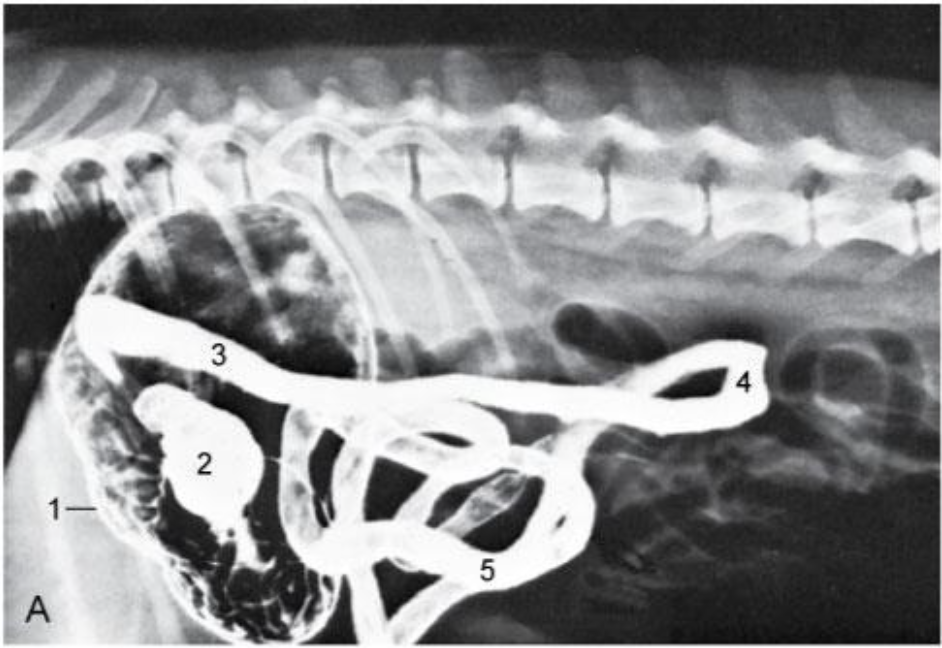

Runs caudally (right side) – Descending duodenum- level of tuber coxae- makes a U- turn –runs obliquely-craniosinistrally (leftside)- continues as the ascending duodenum

Re. Cranial duodenum, topographical position?

Dorsally and laterally lies in contact with the liver and medially by the pancreas